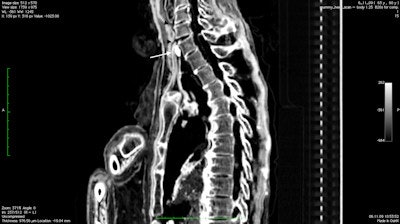

The CT scans of Ramesses III revealed a wide and deep wound in the throat of the mummy, probably caused by a sharp blade. It could have caused immediate death, the authors noted. The injury was roughly 70-mm wide and extended to the bones (fifth to seventh cervical vertebra), severing all soft-tissue areas in the anterior side of the neck. The trachea was clearly cut, and its proximal and distal ends were retracted and separated by about 30 mm. A small, focal cortical interruption at the anterior surface of vertebral body was visible, at the seventh cervical vertebra.

A Horus eye amulet also was found inside the wound, most probably inserted by the ancient Egyptian embalmers during the mummification process to promote healing. The neck was covered by a collar of thick linen layers.

CT revealed a serious wound in the throat of Ramesses III's mummy, directly under the larynx. Copyright: A. Zink.Analysis of unknown man E revealed an age of 18 to 20 years, while an inflated thorax and compressed skinfolds around the neck of the mummy suggests violent actions that led to death, such as strangulation, according to the authors. Furthermore, the body was not mummified in the usual way -- and was covered with a "ritually impure" goatskin, which could be interpreted as evidence for a punishment in the form of a nonroyal burial procedure.

Left: 3D reconstruction of the mummy of Ramses III. Right: The researchers found a flat, irregular, foreign object lodged in the right lower rim of the mummy's wound. It was roughly 15 mm in diameter with a high CT density (2200 HU), similar to a semiprecious stone. Reconstruction of this object showed a "wedjet" (or Horus eye) amulet. The eye of Horus is a magical amulet that served as a metaphor of royal power, protection, and good health in ancient Egypt, they noted. Copyright of both images: A. Zink.The authors believe that unknown man E could well be Pentawere, but they stress that the cause of death has to remain a matter of speculation. In addition, DNA analysis revealed that the mummies share the same parental lineage, strongly suggesting that they were father and son.